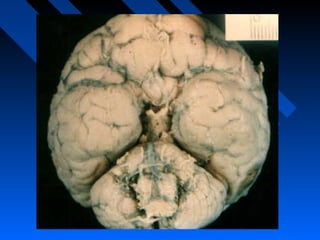

MONSTRUOSIDADEMONSTRUOSIDADE

 ANOMALIA ACENTUADA QUEANOMALIA ACENTUADA QUE

INTERFERE COM O DESENVOLVIMENTOINTERFERE COM O DESENVOLVIMENTO

DO CORPODO CORPO

((AGENESIA DE CÉREBROAGENESIA DE CÉREBRO))

INCOMPATÍVEL COM A VIDAINCOMPATÍVEL COM A VIDA